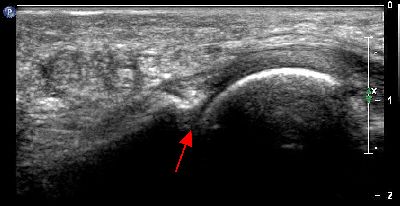

Pannicolo fibrotico intrarticolare

(caso del paziente G.V.)